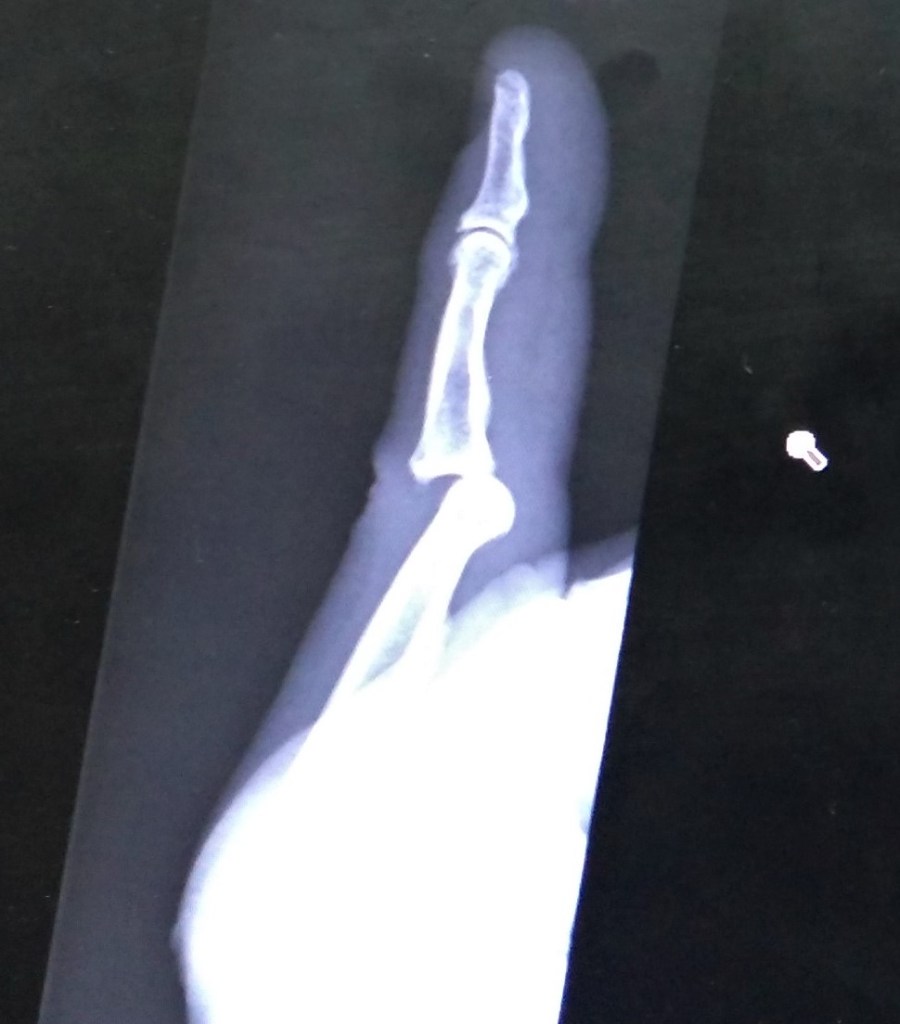

We made it to the clinic a little past 6:45 pm. An x-ray of my finger revealed it was dislocated. I was glad I did not need stitches for my cheek injury.

After trying twice to reset my finger, they splinted it, told me to keep it iced and made an appointment at Teton Orthopedic the next day for further treatment.

The next morning I was told the hand specialist at Teton Orthopedic had the day off. However, when she saw the x-ray, she made a special trip to the office. She was able to pop it in place to my immediate relief! I was then sent to get a more permanent splint. Shortly after noon we were finished!